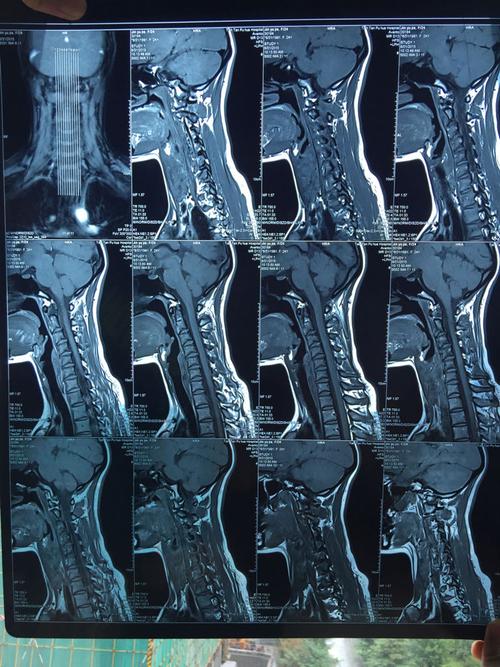

颈椎核磁图片,颈椎核磁共振图片

颈椎病专题(三):带你了解外伤后的颈脊髓损伤

颈椎核磁

颈椎3456向后轻微突出,前几天有呕吐,很严重吗?今天刚照的核磁.

眉县中医院骨二科成功完成-颈后路单开门减压内固定术治疗颈椎管狭窄

颈椎核磁片显示:颈4,5,6,7位颈椎间盘突出!

颈椎核磁共振图片

正常的颈椎核磁图片

正常颈椎核磁共振图

颈椎核磁共振图片图解

怎样看懂颈椎磁共振图

颈椎磁共振图片详解

颈椎核磁图片正常

颈椎核磁图片怎么看

颈椎核磁正常

颈椎核磁解剖

颈椎核磁图谱解析

颈椎的核磁共振的图解

颈椎核磁共振报告

磁共振颈椎神经压迫图